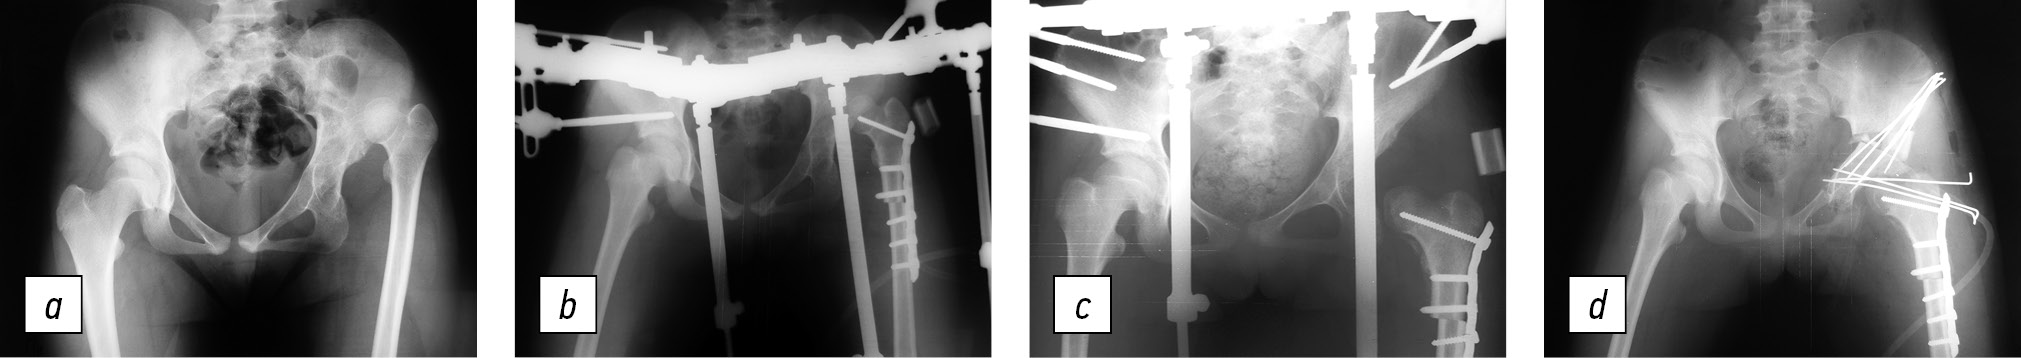

All patients underwent surgery, which consisted of two stages. At stage 1, a rational shortening detorsion–varus osteotomy of the femur was performed with the imposition of a distraction apparatus, which was used to eliminate the residual displacement of the femoral head in the postoperative period. At stage 2, when the femoral head was opposed to the acetabulum, open reduction and pelvic osteotomy with correction of the acetabulum were performed (Fig. 1).

Fig. 1. Radiographs of patient T., 13 years old, with high congenital dislocation of the left hip: a, before the treatment of iliac dislocation, the head of the left femur is located at the iliac wing level, with discontinuity of the Shenton line of 6 cm, acetabular index of 60°, angle of vertical inclination of the cavity 68°, caput–collum–diaphyseal angle of 125°, and anteversion of the femoral neck of 50°; b, stage 1 of surgical treatment included shortening detorsion osteotomy of the femur with the imposition of a distraction apparatus on the pelvis and left thigh. The resected bone fragment (2.5 cm) is located in the subcutaneous tissue in the acetabular zone; c, X-ray image 2 weeks after the distraction start. The head of the left femur was reduced to the level of the lower edge of the acetabulum; d, in stage 2 of surgical treatment, the distraction apparatus was dismantled, and open reduction of the femoral head into the acetabulum and triple osteotomy of the pelvis on the left with transposition of the acetabulum were performed